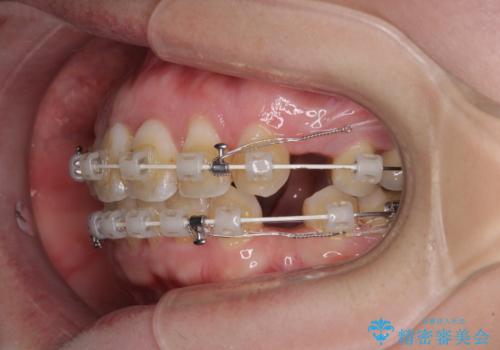

- 出っ歯と口の閉じにくさ、デコボコを気にして来院された患者様です。

口元の突出感を改善するため、上下左右第一小臼歯4本の抜歯を行い、ワイヤー装置による矯正治療を行うこととしました。

上下前歯の距離が大きかったため、上下の歯が接触するまでに時間がかかりました。

それでも目安である2年半で終えることができ、患者様には大変満足していただけました。